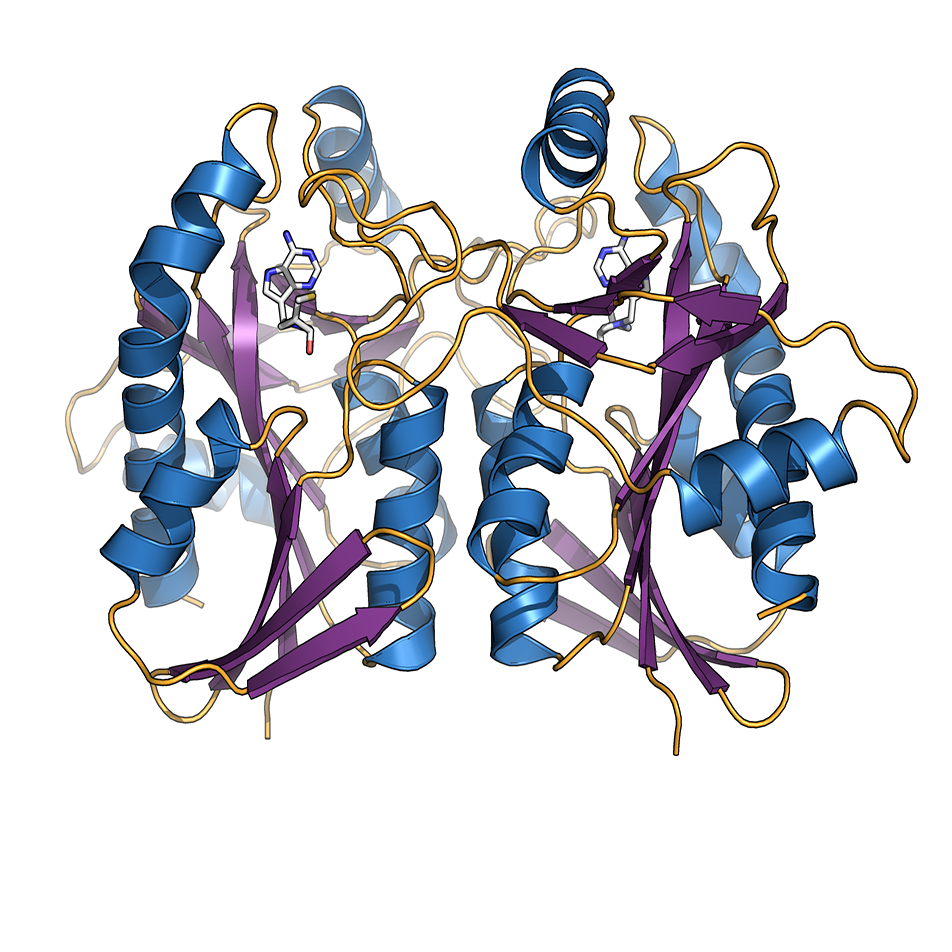

Smarter drug design

An advanced experimental technique linked to high powered computation is becoming an increasingly important tool for MWC researchers developing new drugs.

New insight into an established diabetes target

Facilitating the development of better medicines for diabetes, obesity and cardiovascular disease is a key driver behind some painstaking research at the Maurice Wilkins Centre to

read the full story